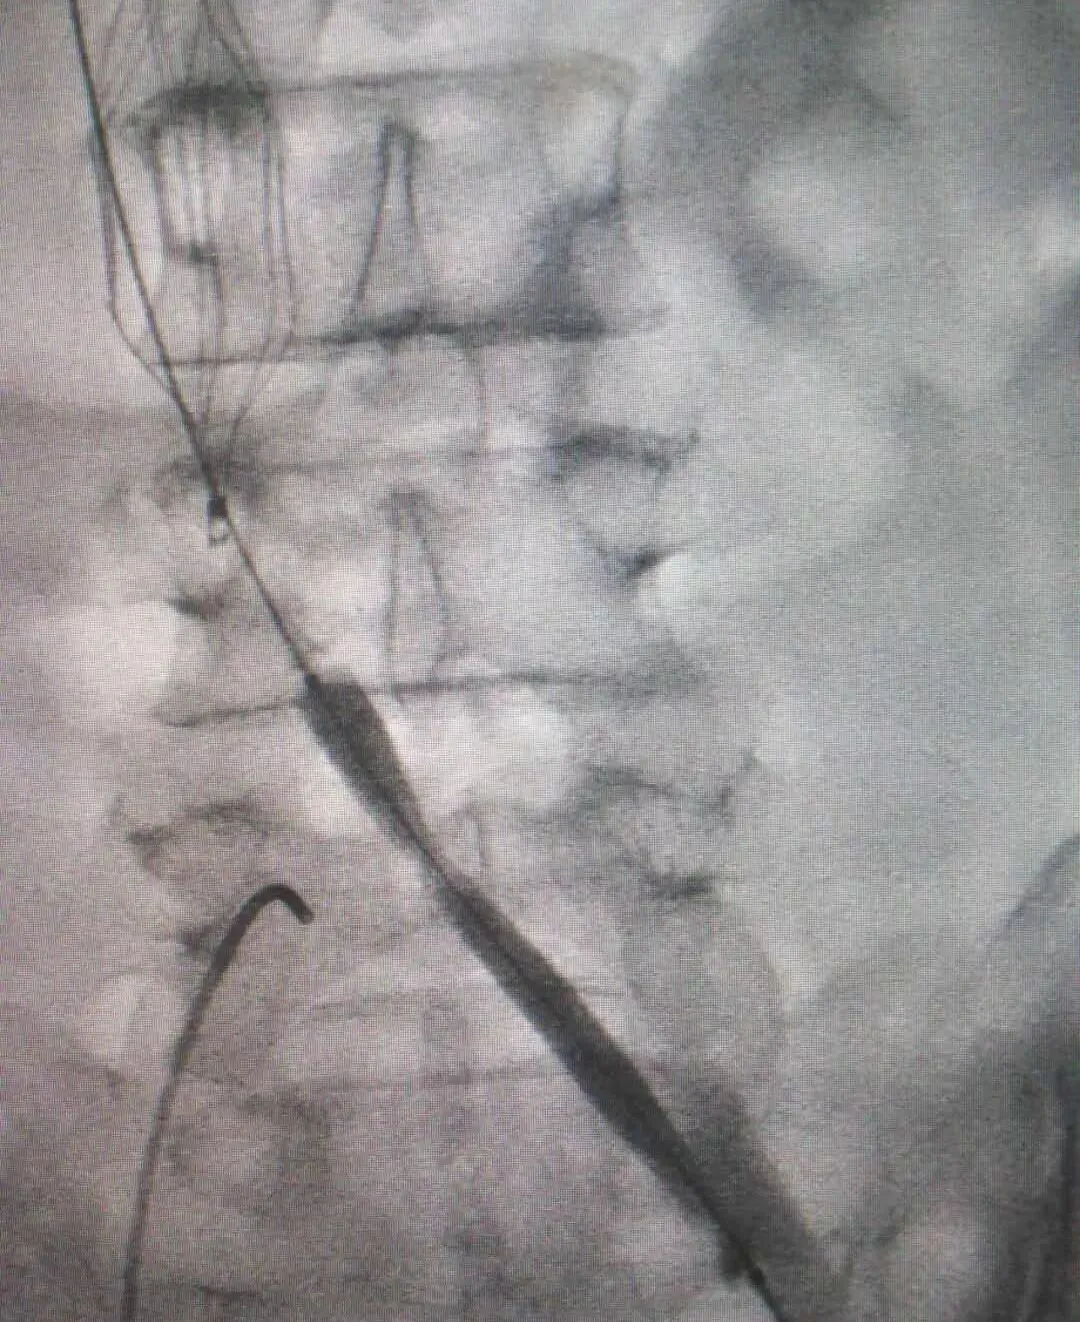

术中造影显示,王大叔左侧股静脉、髂总静脉有长段血栓形成,阻塞范围约有30cm长。由于静脉的血管壁薄,血管闭塞时间长,病变范围广,所以手术的风险极高。丛海波院长和影像科主任兼介入、血管外科负责人侯红军团队决定为其进行“左股静脉切开取栓+左髂总静脉闭塞球囊扩张术”,术中用取栓导管取出40-50毫升血栓,由于髂总静脉开口处血管质地硬,导管无法直接通过,采用导丝导管技术通过了闭塞段,并用球囊逐级扩张。

(球囊扩张过程)